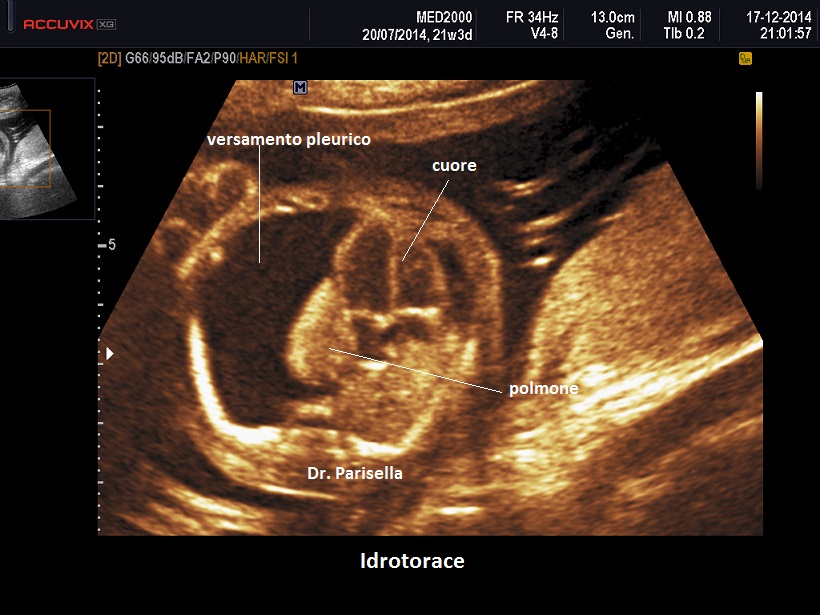

Diagnosi Ecografica

La diagnosi ecografica non offre in genere difficoltà ed è rappresentata da un versamento pleurico monolaterale o bilaterale.

Nelle forme monolaterali si ha shift mediastinico con dislocazione controlaterale del cuore.